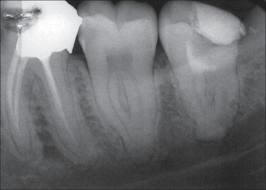

Rx de

molares inferiores mostrando la

disposición de las raíces y sus

conductos. |

| 1º Molar

inferior: El orificio de entrada del

conducto distal se encuentra ensanchado

en sentido buco lingual, debe sospechar

la existencia de un cuarto conducto.

La localización

de un cuarto conducto se lleva a cabo

con la

técnica radiológica de Clark

o por

medio de una lima curvada en distal para

sondear la pared lingual ó vestibular

del conducto distal. Imagen inferior |